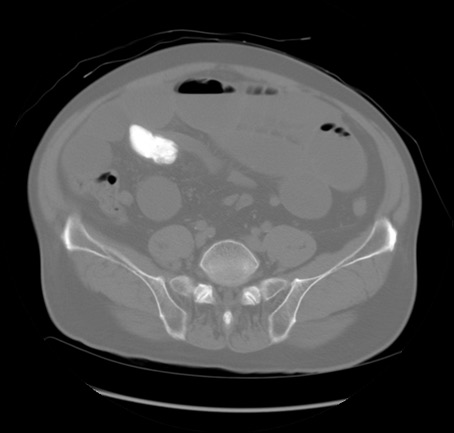

症例20(横断像)

【症例】 60歳代男性

【主訴】 腹部膨満、嘔吐

【現病歴】5日前頃より倦怠感を認め食事量減少し4日前の朝嘔吐、食事摂取困難となった。 3日前近医受診し点滴施行され整腸剤などを処方された。 当日他院を受診し、腹部膨満著明、炎症反応の上昇(CRP10.8、WBC11200)あり、紹介受診となる。

【身体所見】 意識JCS1 受け答えがはっきりしないBP 111/57mHg、 P 67bpm、、BT35.2°C、SpO2 97%(RA)、 腹部:膨隆、打診で鼓音あり、全体的に圧痛有り、腸蠕動音(-)、反跳痛ははっきりせず。

【データ】WBC 11400、CRP 14.20